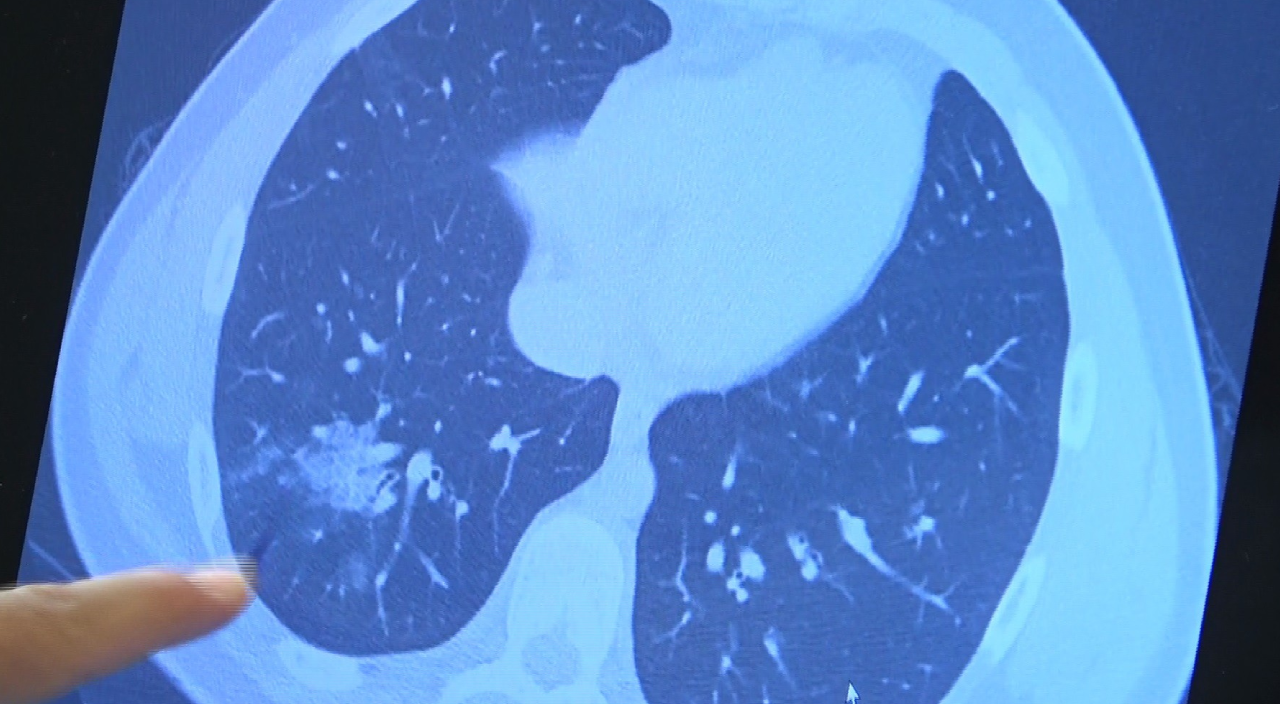

Bazı vatandaşlar hâlâ aşı olmakta tereddüt etmeye devam ederken korona virüs çocuk grubundaki hastaları da etkilemeye başladı. Prof. Dr. Şevket Özkaya ise aşı olabilecek yaş grubundaki çocukların bir an önce aşılanması gerektiğine vurgu yaptı. 14 yaşında, kronik rahatsızlığı olan ve akciğerlerinde tahribattan dolayı ciddi öksürük, ateş ve nefes darlığı çeken bir hastanın akciğerlerini inceleyen Prof. Dr. Özkaya, "14 yaşındaki kronik rahatsızlığı mevcut olan bir genç hastamızda ciddi akciğer tutulumları var. Her iki akciğerinde de yaygın buzlu cam ve konsolidasyon alanları var. Bu yaştaki çocuklarda beklemediğimiz bir durumdur. Okullarımızda da bu risk var. Okullarımızın açık kalmasının ve sağlık sistemimizin kitlenmemesi için mutlaka aşı olmalıyız. Çocuklarımıza rol model olmalıyız. Şu anda hastanelerimiz hastalara yetişebiliyor. Yatak sayımız yeterli. Ancak kontrollü sosyal hayatımızı düzene sokmadıkça ve aşı olmadıkça, gelecekte hastanelerde yatak sayısı sıkıntısı çekebiliriz" dedi.